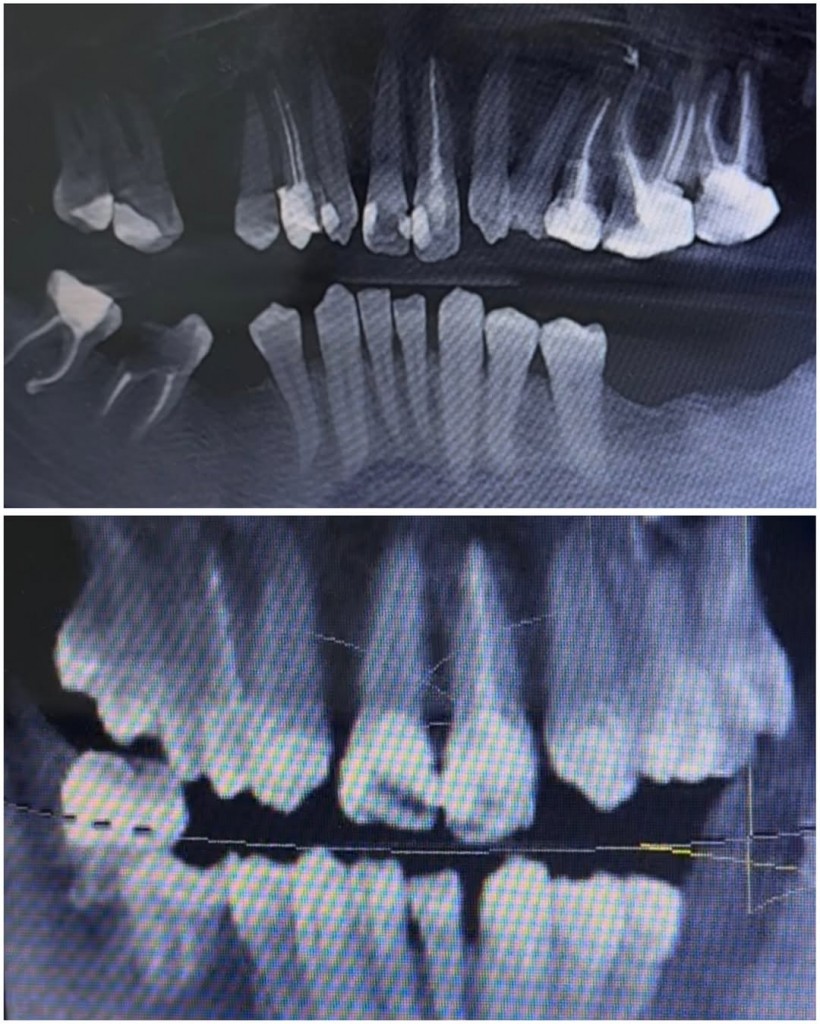

В данном клиническом случае мы показываем как можно эстетически подкорректировать врожденные аномалии. У пациента с рождения отсутствуют вторые резцы, их место заняли клыки.

Визуально мы видим несоответствие формы,  наличие промежуткав между зубами, а также дисколорит.

Было предложено исправить данный дефект с помощью коронок из диоксида циркония.